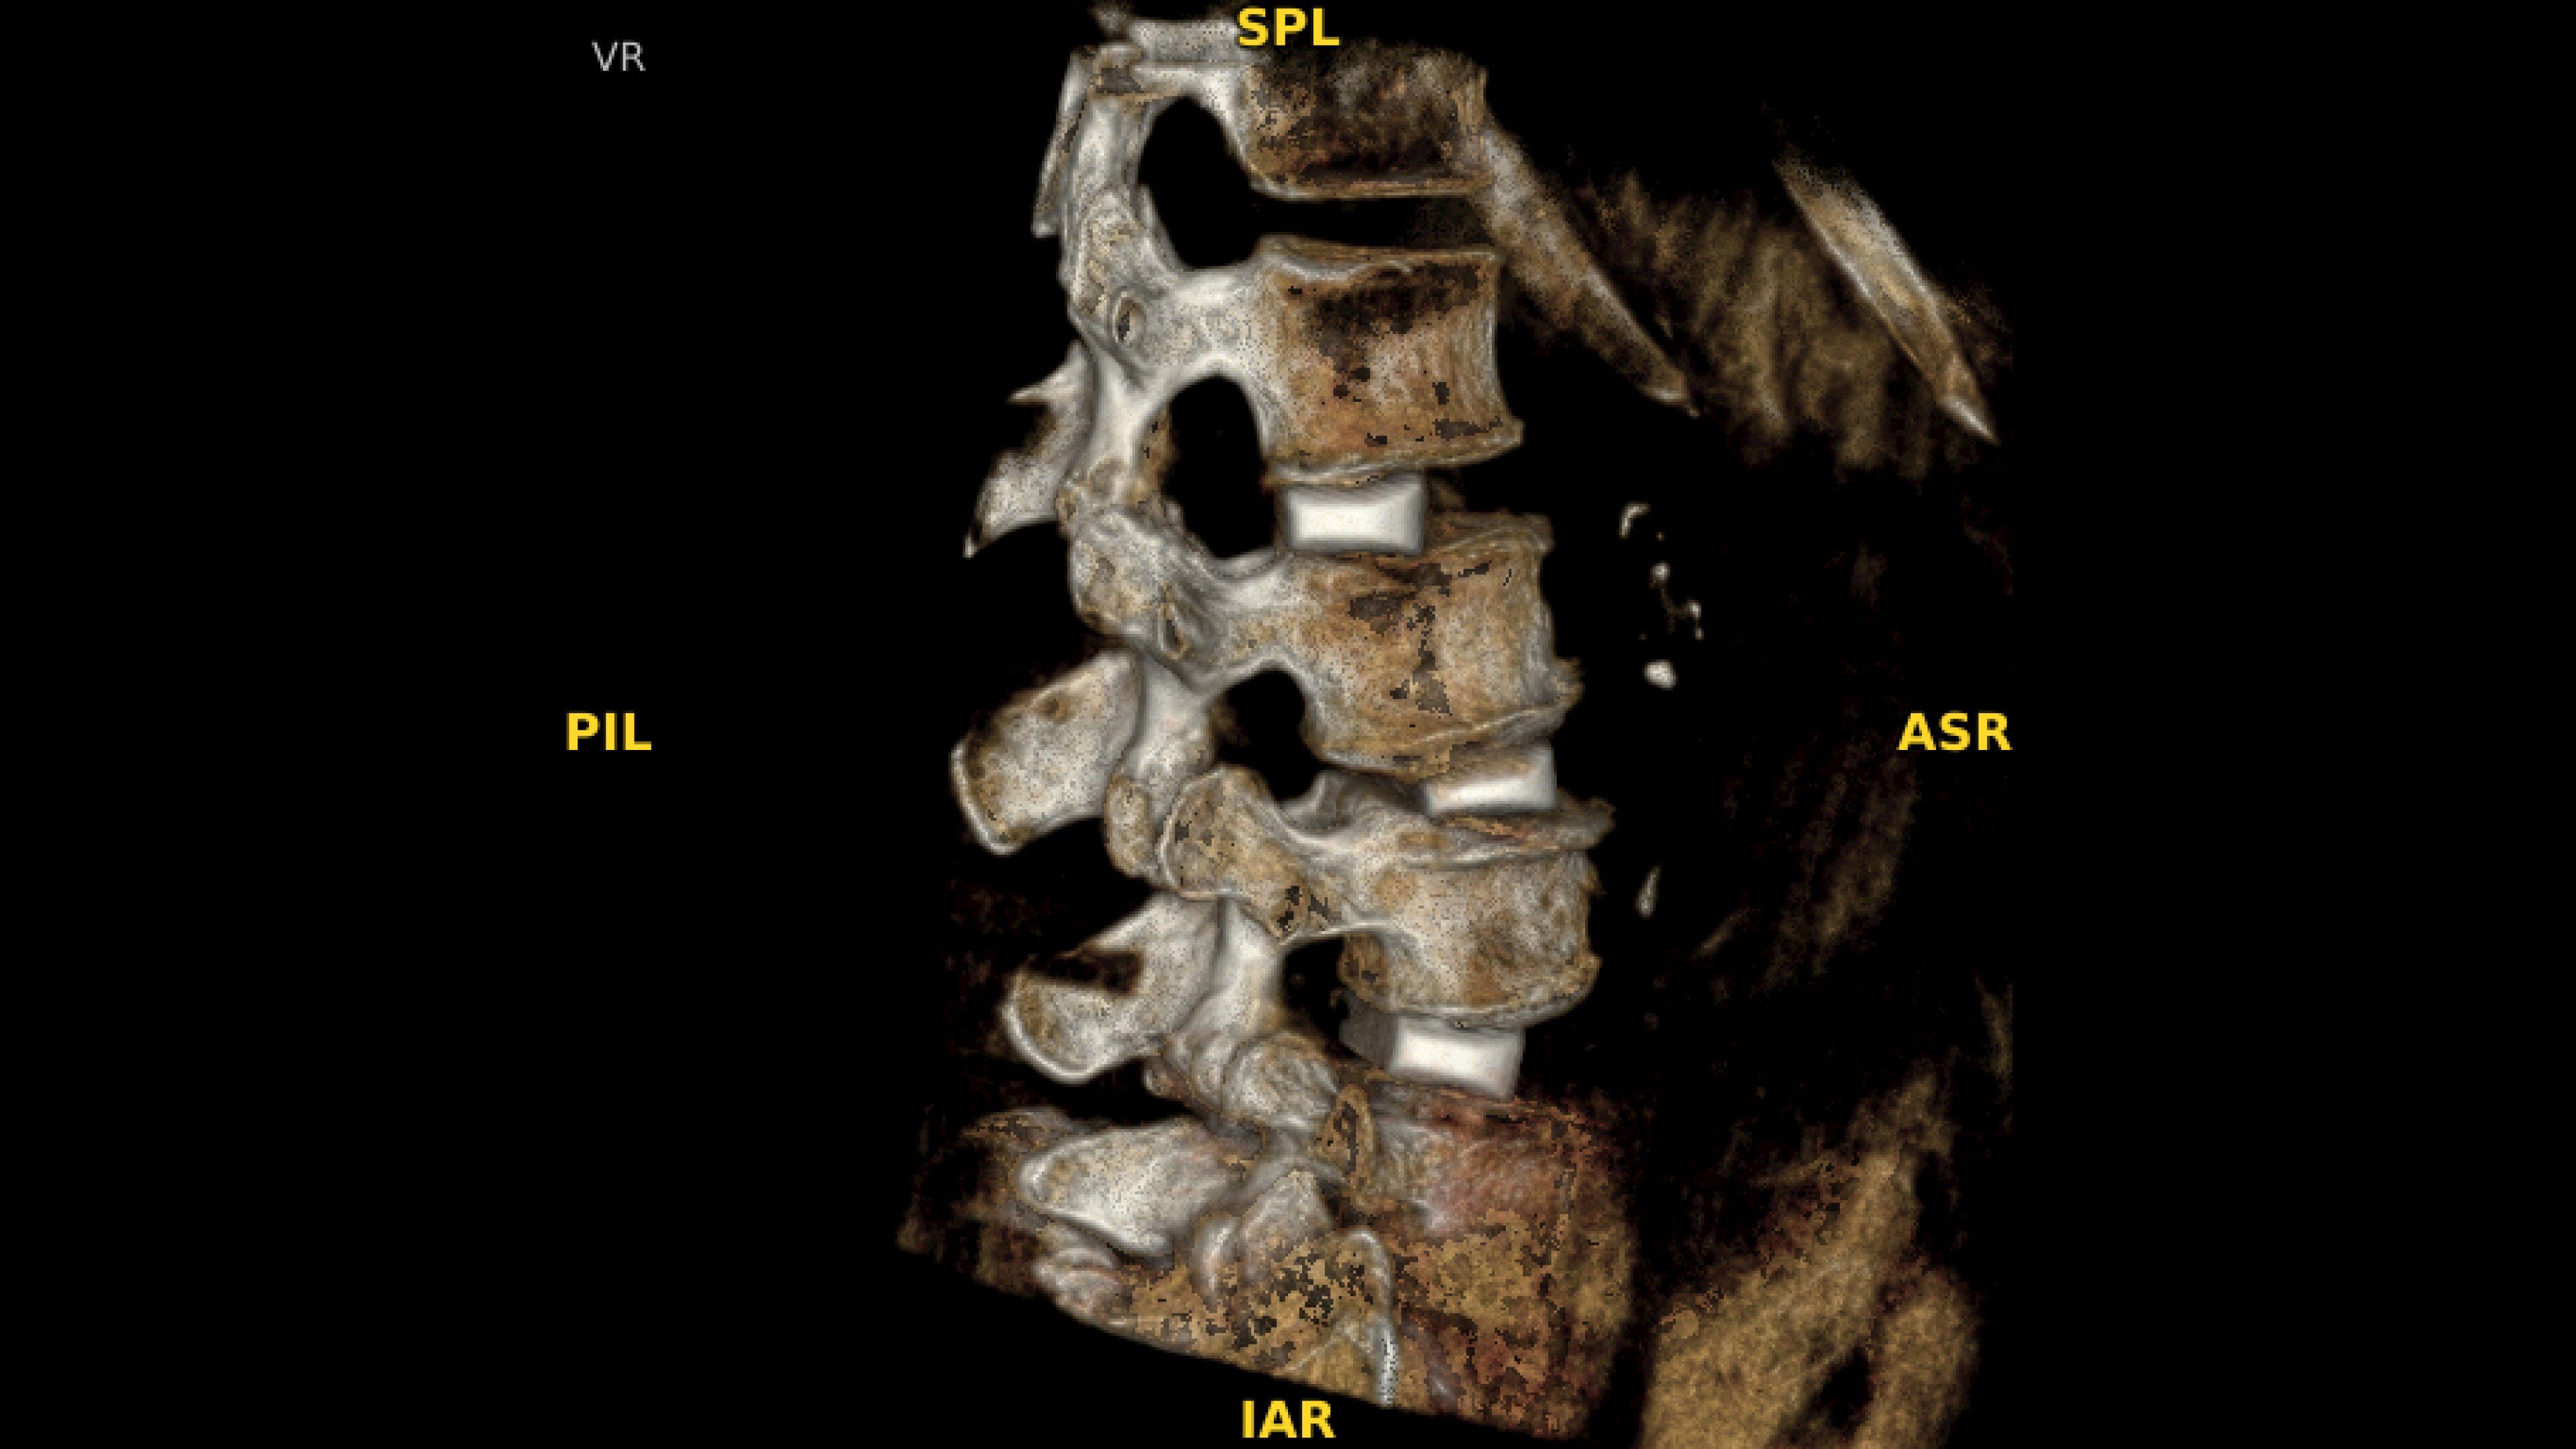

With OEC 3D, comprehensive imaging coverage of 19 cm x 19 cm x 19 cm 3D volumes and exceptional 2D images enables viewing several levels of the spine in the operating room.

The OEC 3D presents five perspectives: Axial, Coronal, Sagittal, MIP, and VR, on a 4K display for clear and detailed review of 3D volumes and 2D images

Review screws with automatic detection and numbering, manually label spine levels, and visualize spinal curvature alignment with Spine Suite, an optional application available with OEC 3D.